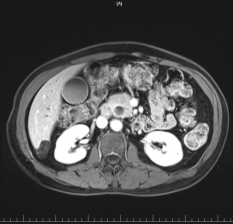

患者李大爷,因急性梗阻性胆管炎到我院就诊收住急诊科,完善相关检查后发现胆管下段狭窄 (炎性病变病低位胆道梗阻,肿瘤性病变待排),术前肿瘤标记物CA199 10.44U,经院内会诊后,患者转入普外二科继续下一步治疗。

用经口电子胆管内窥镜进入胆管探查后,未探及明显隆起及肿物,考虑胆管下段炎性狭窄,拟留置覆膜胆道支架3月后返院复诊拔除支架。